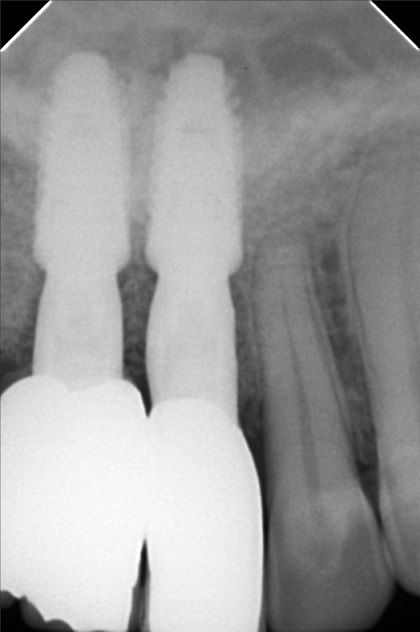

Edit Record Check our patient data records. Add patient information Patient Info Profile picture Last Name First Name Middle Name Birthdate Age Street Barangay City Country Zip Code Contact number Email Procedure 01/30/21 ICF - check up Feb 8,2021 - Implant 11/03/22- OP/OZONE/PAD feb,20,2021- removal of suture march 31,2021- LC 11 & 21 07/31/21 repair 41 zirconia resto 36CAOH/46 CAOH/43/34 OP June 4,2022 - OP / Xray 05/13/23- OP(Moderate); xray; ozone Oct 1 2023 op with air polisher noticed gum recession Removal of fiber splint on 42/43 05/07/24 Air polisher Xray OP 06/15/24 connective tissue graft harvested side: upper right quadrant w/ suture- monofilament absorbable 4/0 donor site: implant #41/32 buccal and lingual combination of monofilament absorbable 4/0 and nylon 6/0 non absorbable 06/22/24 check up 06/29/24 suture removal File raposa_donna_kelly_3.jpg File 2 raposa_donna_kelly_2.jpg File 3 raposa_donna_kelly_1.jpg File 4 donna_kelly.jpg File 5 june_42022.jpg File 6 raposa_donna.jpg File 7 raposa_donna_02.jpg File 8 img_2831.jpg File 9 File 10 File 11 File 12 File 13 File 14 File 15 File 16 File 17 File 18 File 19 File 20 Retain Record Retain Record Yes No Save Your Changes